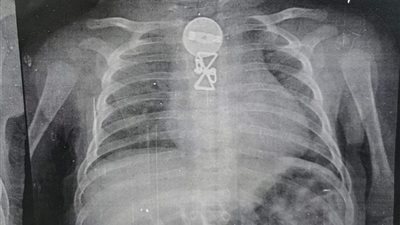

استخراج جسم غريب من رئة طفل بمستشفى الأطفال التخصصى في بنها (صور)

نجح فريق طبي بمستشفى الأطفال التخصصى ببنها برئاسة الدكتور محمد محمد متولي استشاري جراحة الأطفال ونائب المدير العام بمعاونة نخبة من أطباء الجراحة، والتخدير بالمستشفى وهما كلا من الدكتور مصطفى حمد، والدكتور محمد سعده، والدكتور وليد محمد، والدكتور اسلام حجاب بإستخراج جسم غريب من طفل يبلغ من العمر ثلاثة أشهر.